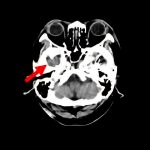

断層撮影

手術前1